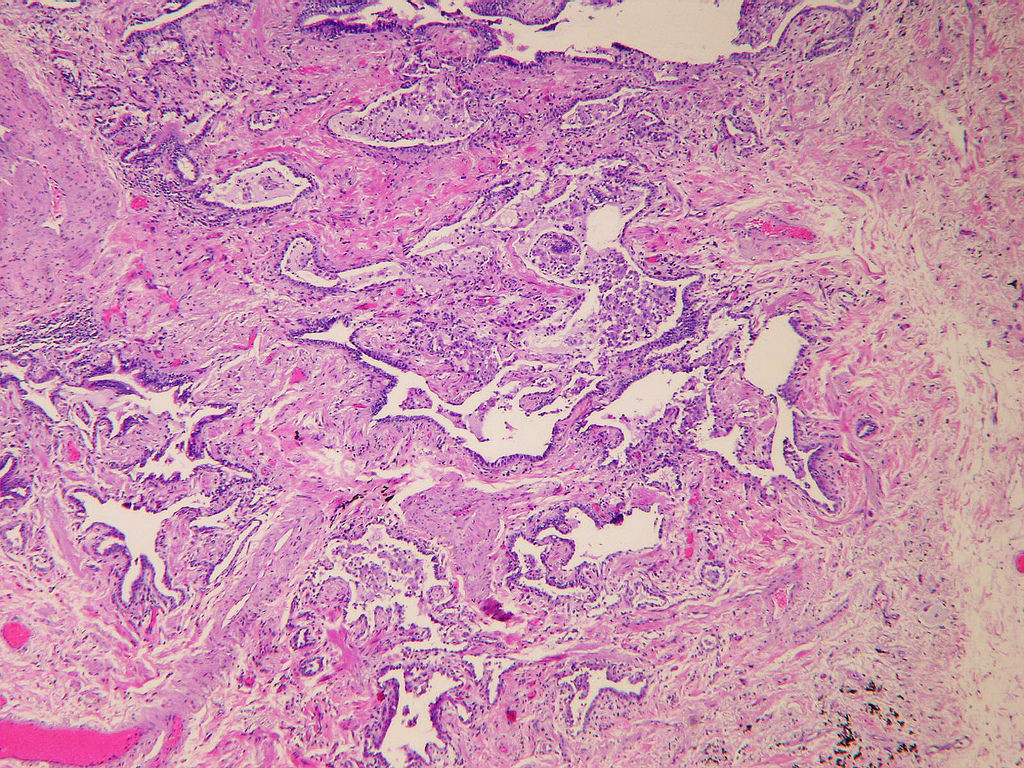

Microscopic (histologic) description

- Major findings are consistent with UIP pattern (Am J Respir Crit Care Med 2022;205:e18)

- Patchy dense fibrosis with architectural distortion

- Lesion representing UIP pattern is mainly composed of hyalinized collagen

- Often destructs alveolar architecture

- Smooth muscle and elastofibrosis are often present

- Only mild infiltration by inflammatory cells should be seen (usually near areas of honeycomb change)

- Honeycombing: cystic spaces lined by bronchiolar epithelium and fibrotic wall

- Predilection for subpleural and paraseptal lung parenchyma

- Spatial heterogeneity (dense fibrosis alternating with areas of the uninvolved lung) is evident on low power

- Normal lung parenchyma can remain in the center of the lobule

- Fibroblastic foci

- Active fibrotic lesions composed of myofibroblasts

- Aggregation of spindle cells with gray to pale purple matrix adjacent to dense fibrosis

- Absence of features that suggest an alternate diagnosis

Microscopic (histologic) images

Contributed by Akira Yoshikawa, M.D. and Yale Rosen, M.D.